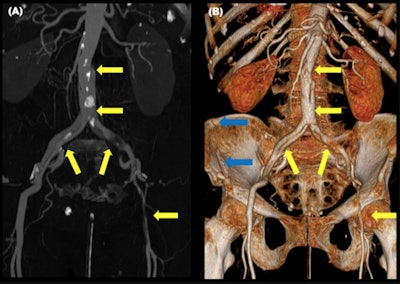

Abdominal wall hernias occur because of the shearing forces through the myofascial layers of the abdominal wall during the sudden deacceleration and the high increase in the intraabdominal pressure. They occur through the weakest anatomical sites of the abdominal musculature. Multiplanar reformation should be performed to increase sensibility.

"Although they are misdiagnosed clinically, their presence indicates the violence of the accident and they are associated with a high risk of surgical intraabdominal injuries; either herniated intraabdominal structures or structures far from the herniation site," they explained. "Other abdominal wall injuries include soft tissue contusion or direct muscle rupture."